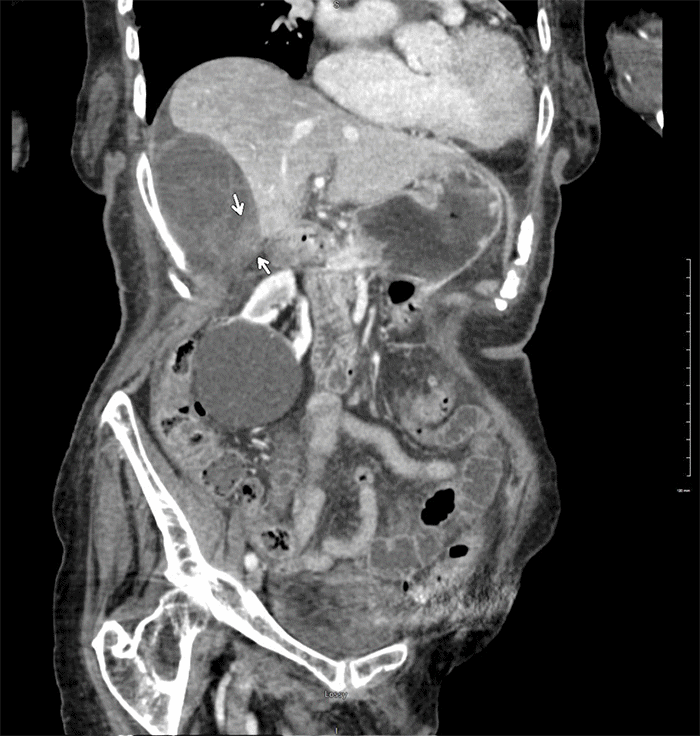

Figure 2. Coronally Reformatted Abdominopelvic CT. Published with Permission

Image demonstrates a significantly distended gallbladder with profuse pericholecystic edema, ill-defined hypoenhancing, and thickened wall, wall sloughing, and hemorrhage in keeping with ischemic changes. Thickened soft tissue density at the pedicle suggested gallbladder volvulus (arrows)

On gross pathology of the specimen, the gallbladder wall was found to be diffusely necrotic. The cystic duct was thickened, firm, and without an apparent patent lumen (Figure 2). No obstructing neoplasm was identified.